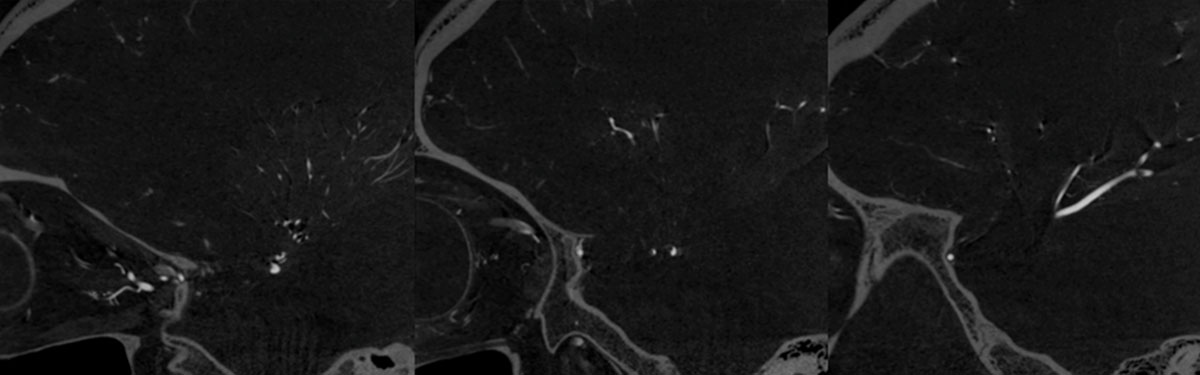

CT – CTA - CTP

DSA